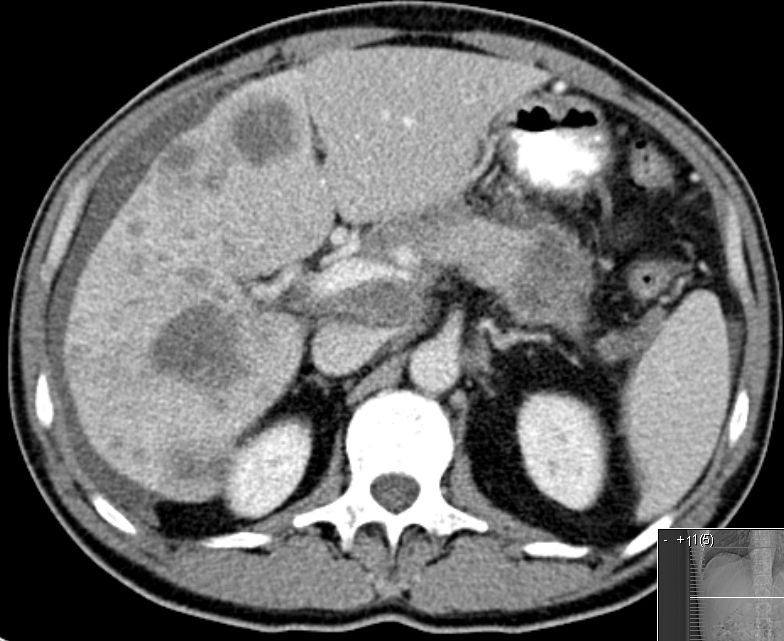

| Pankreasschwanz | Pankreasschwanz-Karzinom, Leber- und Lymphknotenmetastasen![]() | |

| Pankreasschwanz | 55-jähriger Mann mit Pankreasschwanz-Karzinom, Lebermetastasen, Ascites![]() | |